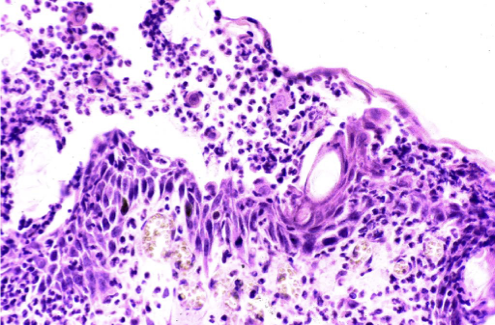

How does pemphigus foliaceus present histologically?

Superficial micropustules, also extending to hair follicles

Acantholysis (acantholytic keratinocytes present)

Minor dermal inflammatory infiltrate